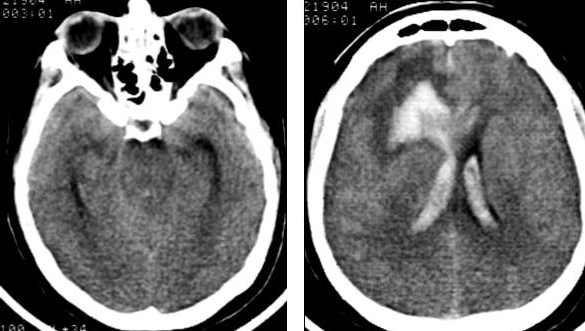

При поступлении состояние оценивалось по шкале Hunt-Hess в 4 балла. Уровень сознания соответствовал сопорозному. Выявлялся выраженный менингиальный синдром. Орально-стволовый синдром проявлялся двухсторонним сужением зрачков, ослаблением фотореакции, ограничением произвольного и рефлекторного взора вверх. Выявлялся левосторонний гемипарез до трех баллов.При компьютерно-томографическом (КТ) исследовании головного мозга были выявлены признаки массивного САК, внутримозговая гематома в лобно-височной области справа с распространением на колено мозолистого тела и прорывом крови в желудочковую систему. Базальные цистерны компремированы (Рис. №2).

Через 24 часа после поступления при ангиографии была выявлена аневризма ПМА-ПСА справа (Рис. №1) и произведена операция: треппинг-клипирование аневризмы ПМА-ПСА справа (выключена шейка аневризмы вместе с ПСА), с частичным удаление внутримозговой гематомы правой лобной доли и удалением костного лоскута с пластикой твердой мозговой оболочки с целью наружной декомпрессии.